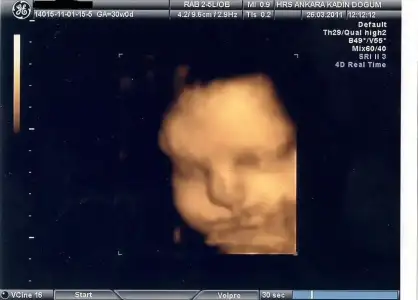

28.haftada bu kadarsa 4 kilo doğar maşallah